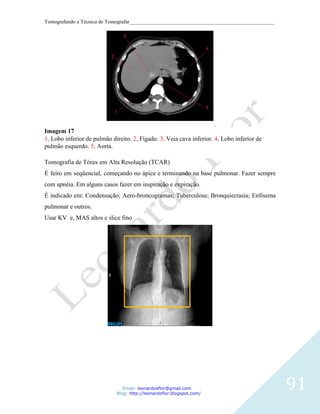

Email: leonardosflor@gmail.com

Blog: http://leonardoflor.blogspot.com/

102

Tomografando a Técnica de Tomografar_______________________________________________________

Os ductos drenam para estruturas chamadas cálices renais menor e maior. Cada rim tem 8-

18 cálices menores e 2-3 cálices maiores. O cálice renal menor recebe urina dos ductos